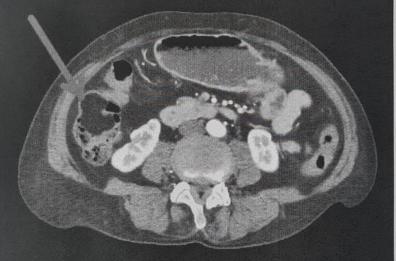

Corato, va in ospedale per un mal di pancia e le scoprono un grosso tumore benigno al colon